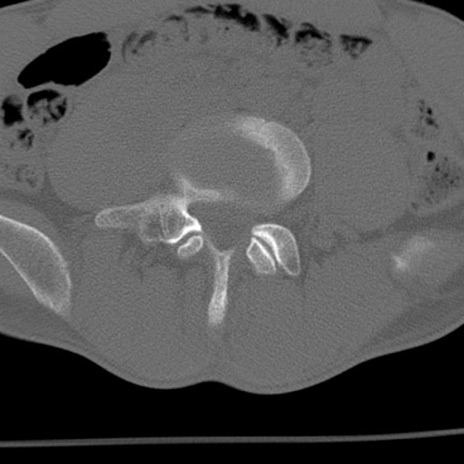

症例3 腰椎CT(横断像)

腰椎CT